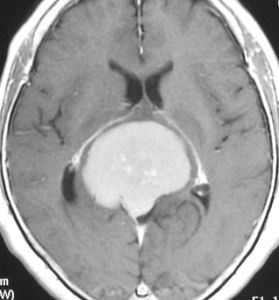

典型的な髄膜腫

この髄膜腫は中程度の大きさのものです。円蓋部髄膜種という最も多い最も手術の簡単なタイプです。麻痺や失語症やてんかんなどの症状はありません。とても美しくて若い女性の髄膜腫でしたが,子供に遺伝はしませんし,癌などと違ってタバコなどこれといった原因がなくて発生するものです。

MRIでの髄膜腫の見え方は撮影の仕方によっていろいろです。左からT1強調画像,T2強調画像,フレア画像といいます。腫瘍の横に小さく白い領域がありますが,これは脳の腫れた部分で脳浮腫といいます。髄膜腫があると周囲に脳浮腫が生じることがあります。

最も見やすいのが,ガドリニウム造影剤を注射して撮影するものです。一般的に髄膜腫は造影剤で白く映し出されます。この腫瘍は左脳側にあります。MRIの軸面という輪切りの写真では左右が逆になりますから注意してください。脳を下から見た図になっています。MRIはいろいろな方向から腫瘍を見ることができますが,右は冠状断という正面から見た図です。よく見ると腫瘍の上と下のはじっこに線状に糸を引いたように造影される部分があります。これをテールサイン(しっぽのサイン)といいます。腫瘍が硬膜に沿って延びている可能性があることを示しています。